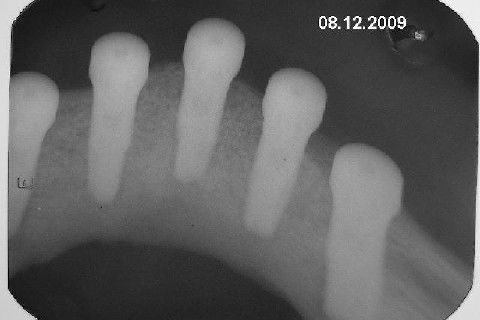

Protocolo Inferior com 5 Implantes - Parte I - Planejamento + Cirurgia

Apesar da boa adaptação e estética satisfatória, a principal queixa da paciente era a instabilidade da prótese inferior, como sempre ocorre nestes casos...atrofia do rebordo alveolar e perda da função mastigatória.